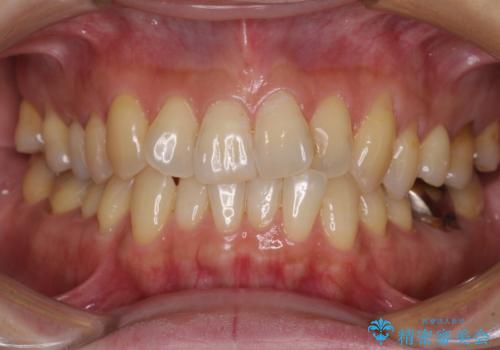

- 前歯のクロスバイトが気になり、インビザラインによる矯正治療を希望して来院された患者様です。

上顎側切歯(上の真ん中から2番目の歯)が舌側転位している場合、インビザラインでは仕上げきれないことが多く、更には無理して動かそうとすると歯髄壊死を起こすリスクが高いと言われています。

インビザラインで歯列を移動する前に、上顎前歯をワイヤー矯正で整え、その後上下歯列をインビザラインにて矯正治療を行うこととしました。

舌側転位している側切歯特有の、切縁の位置が不揃いであったり、根元が内側に引っ込んだ状態であったりという、インビザライン独特の仕上がりになることなく、きれいに整った歯列とすることができました。